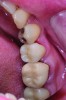

Fig 2. Final zirconia restoration.

Figure 2

Digital dentistry is a reality in modern dental practice. For instance, the use of monolithic zirconia restorations has increased in popularity. These are high-strength, all-ceramic solutions that require only 0.5 mm of occlusal reduction, making monolithic zirconia restorations ideal for posterior teeth with short clinical crowns such as second molars (Figure 2). These types of restorations are always milled, which means that the information the dentist sends to the laboratory must be digitized. The restoration is designed using CAD/CAM technology and then milled.